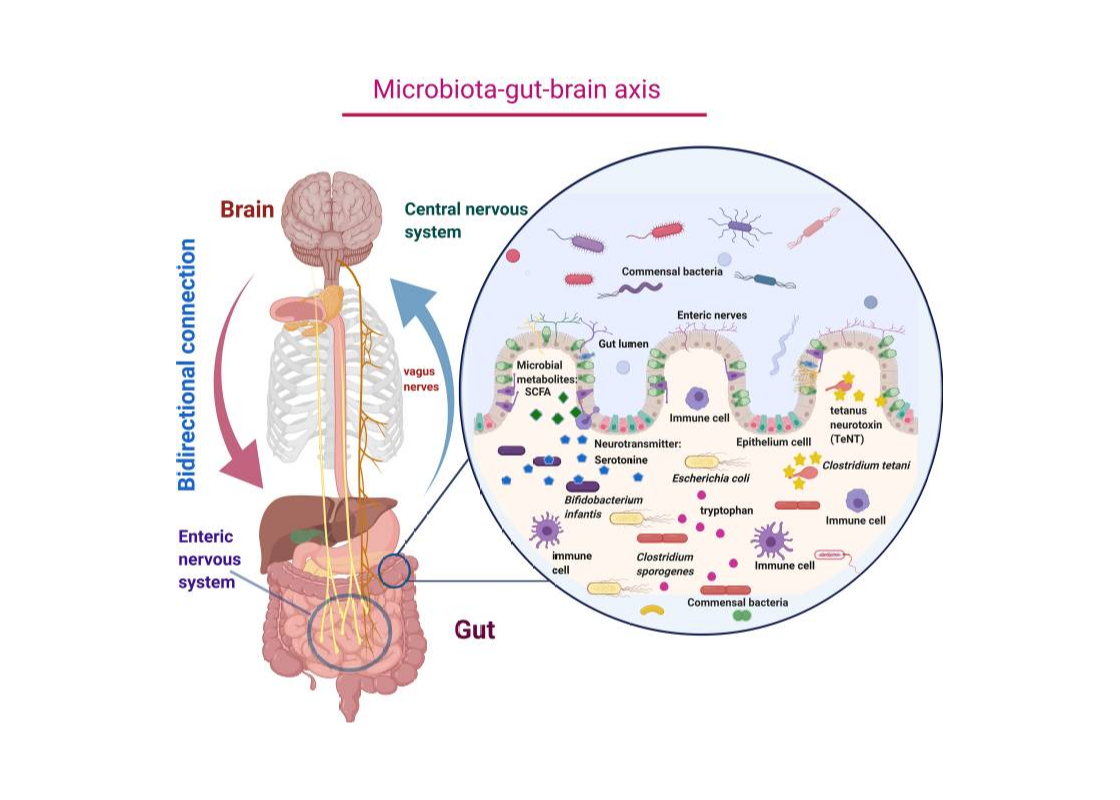

تشير الأبحاث الحديثة إلى وجود تواصل ثنائي الاتجاه بين الأمعاء والدماغ، يُعرف باسم محور الأمعاء–الدماغ. يتم هذا التواصل عبر عدة مسارات، منها الجهاز العصبي (وخاصة العصب المبهم)، والجهاز المناعي، إضافة إلى مواد كيميائية تنتجها بكتيريا الأمعاء.

هذا المحور يفسر كيف يمكن لاضطرابات الأمعاء أن تؤثر على المزاج، السلوك، والانتباه، وكيف يمكن للتوتر والضغوط العصبية أن تنعكس بدورها على الجهاز الهضمي.

شكل توضيحي لمحور الأمعاء–الدماغ يوضح الاتصال ثنائي الاتجاه بين الجهاز العصبي المركزي (CNS) والجهاز العصبي المعوي (ENS) عبر العصب المبهم، ودور النواقل العصبية والمستقلبات البكتيرية مثل الأحماض الدهنية قصيرة السلسلة (SCFA).

شكل توضيحي لمحور الأمعاء–الدماغ يوضح الاتصال ثنائي الاتجاه بين الجهاز العصبي المركزي (CNS) والجهاز العصبي المعوي (ENS) عبر العصب المبهم، ودور النواقل العصبية والمستقلبات البكتيرية مثل الأحماض الدهنية قصيرة السلسلة (SCFA).

المصدر: Taniya وآخرون، 2022 – Frontiers in Cellular and Infection Microbiology.